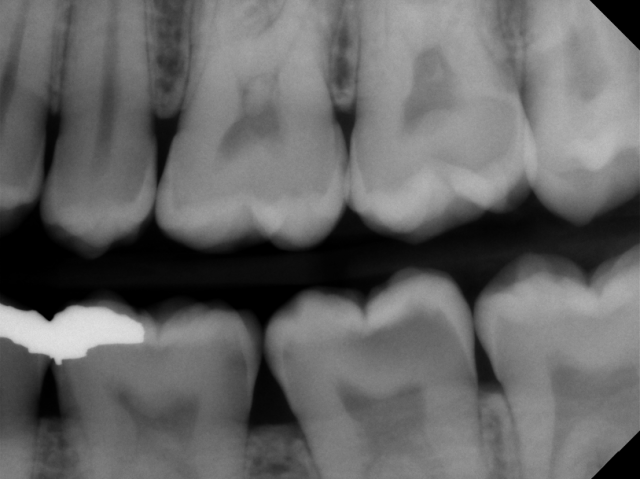

- Single visit caries removal. This is the most common method of removing deep carious lesions. This is most effective when the risk of a pulpal exposure is minimal.

- Stepwise caries removal. In cases where pulpal exposure may result from a single-step caries excavation, a “stepwise” approach can be attempted. In the stepwise approach, most of the affected dentin is removed but some affected dentin close to the pulp is left. A provisional restoration, typically in glass ionomer or RMGI, is placed and a second appointment is scheduled to remove the provisional restoration and remaining affected dentin. When a stepwise approach is taken, the isolation of the carious lesion from the oral cavity changes the composition of the bacteria in the carious lesion, making pulpal exposure less likely during the second excavation appointment.

- Indirect pulp cap. Similar to a single-visit caries removal, the indirect pulp cap involves removing the carious lesion and placing a material that protects the pulp and helps promote secondary dentin formation. This can be considered when pulpal blushing is evident after caries excavation, and is especially useful for young immature teeth with an open apex.

- Direct pulp cap. In the event of a pulp exposure, the exposed pulp is covered with a medicament or restorative material that helps with the formation of a dentinal bridge. Direct pulp capping has been a controversial treatment, with many variables affecting the success rates. Generally, direct pulp capping is more successful if pulpal exposure is due to a mechanical exposure rather than a carious exposure.